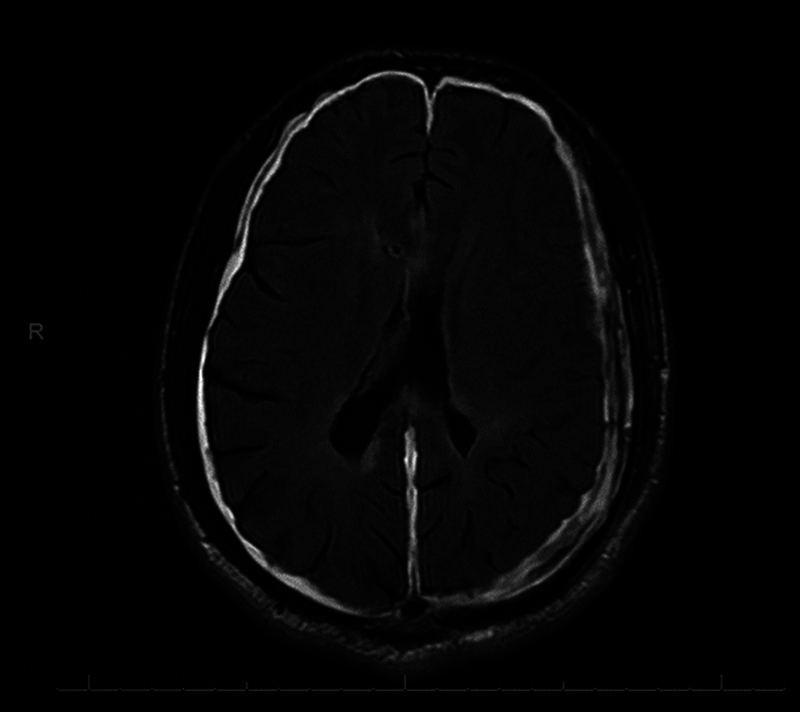

背景先天性输水管狭窄(CAS)是一种罕见的变异,被称为成人发病的CAS,其特征是在成年期出现症状。病例描述一名35岁男性主诉急性头痛和呕吐。脑磁共振成像显示急性脑积水由于输水管网。病人接受脑室腹腔分流术治疗,情况良好。他的病情因过度分流而并发硬膜下血肿,通过额顶骨开颅治疗,最终他接受了可编程瓣膜翻修。结论成人导水管狭窄的假说有待进一步研究。这将有助于阐明无症状儿童期,并通过早期识别晚期CAS,潜在地减少并发症。

Background  A rare variant of congenital aqueductal stenosis (CAS) is known as adult-onset CAS, characterized by the emergence of symptoms during adulthood. Case Description  A 35-year-old man presented complaining of acute-onset headache and vomiting. Magnetic resonance imaging of the brain revealed an acute hydrocephalus due to an aqueductal web. The patient was treated with a ventriculoperitoneal shunt and doing well. His condition was complicated by subdural hematoma as a result of overshunting, which was treated by frontoparietal craniotomy and eventually, he underwent valve revision to a programmable valve. Conclusion  Additional research is needed to gain a deeper understanding of the hypothesis related to adult aqueductal stenosis. This will help shed light on the asymptomatic childhood phase and potentially reduce complications by identifying late CAS early.